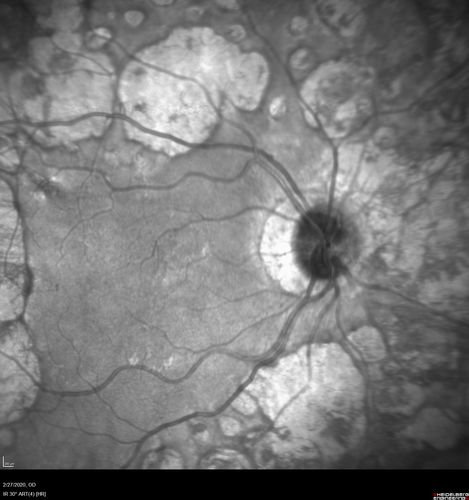

Heavy Panretinal Photocoagulation for Proliferative Diabetic Retinopathy about 40 years ago

64 year old female - images from 2018 - heavy PRP about 30 years ago

VA 20/20 OD, 20/50 OS